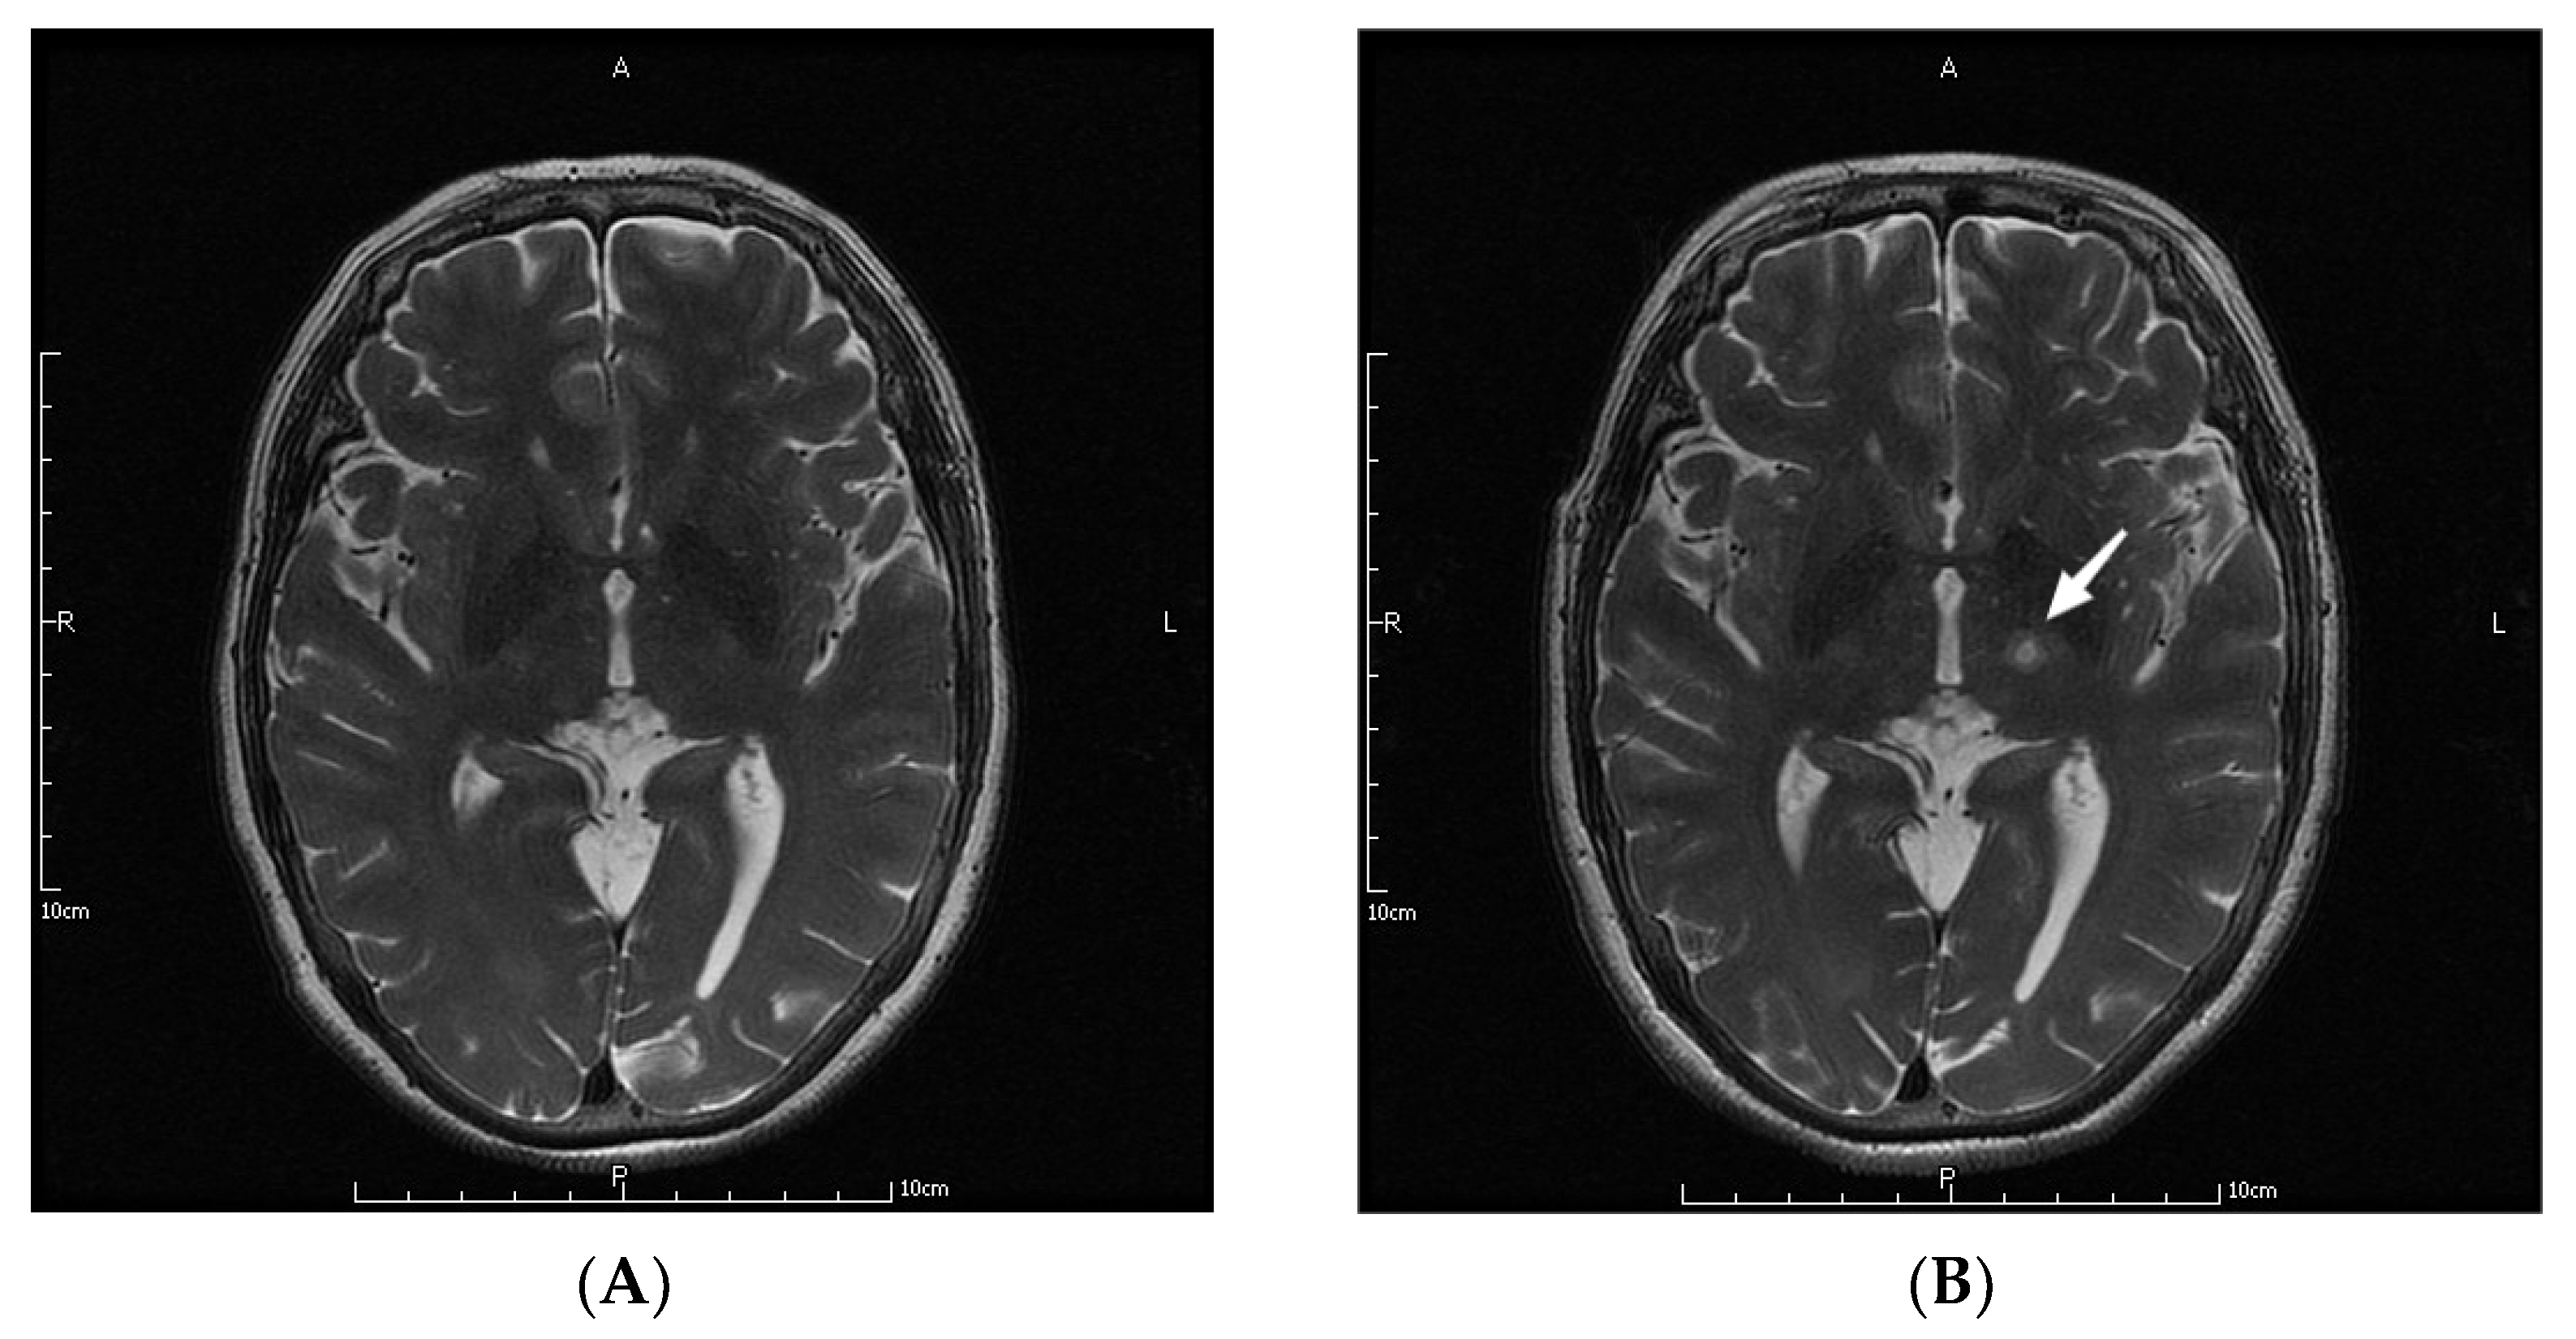

The parameters in the MRgFUS surgery were as follows: the mean ablation time of the 9 patients was 6.22 ± 2.64 s, and the average maximum temperature was 57.89 ± 1.36 °C. Figure 1 shows the MRI images of the patient No. 3 before, during, and at one month, three months, and one year after the operation.

Figure 1.

MRI images of a patient before (A), during (B), and at one month (C), three months (D), and one year (E) after the operation. The letters in the pictures are abbreviations of anterior (A), posterior (P), left (L) and right (R). The white arrow pointed to the lesions created by MRgFUS Vim ablation.